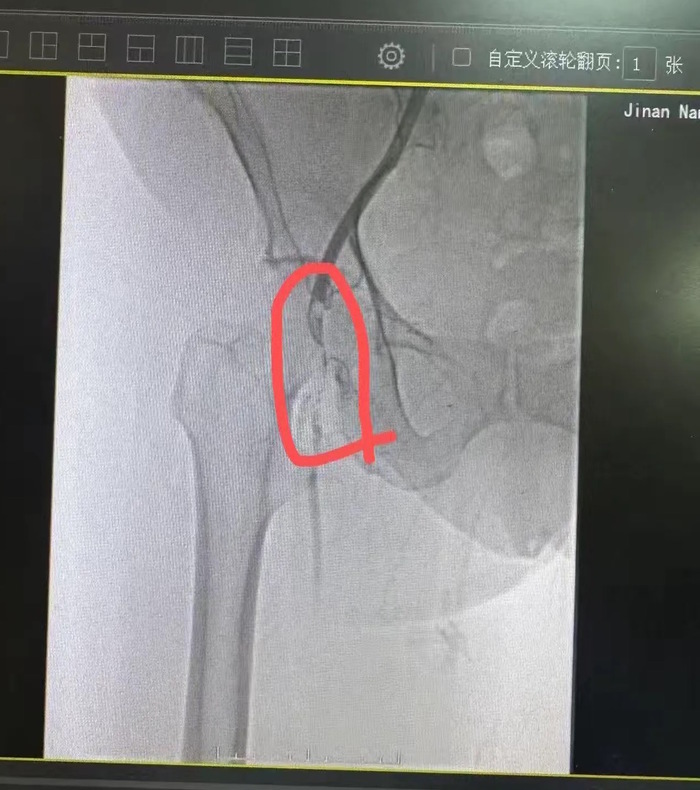

入院后,济南市南山人民医院血管外科团队迅速完善术前检查,为手术做好充分准备。术中,通过造影技术清晰显示患者股动脉栓塞部位及程度,证实了急性股动脉栓塞的诊断。医护团队采用经皮股浅动脉吸栓治疗方案,精准清除血栓,恢复下肢血流。